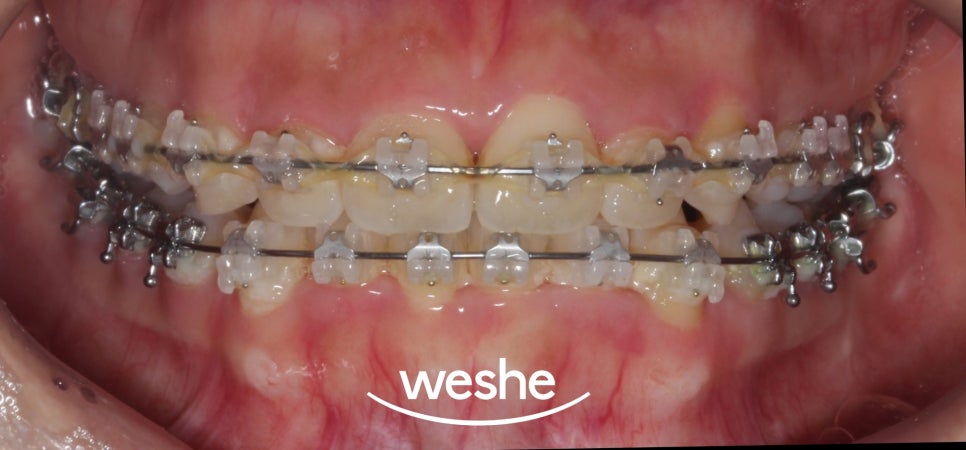

초진

20250612

준비한 예시 사진을 보면

교정 치료를 진행 중인 것을

알 수 있습니다.

브라켓을 부착했을때는

음식 찌꺼기가 자주 끼는 일이

생기곤 합니다.

구강 검사 결과,

치면에 세균막이 관찰됩니다.

브라켓 주변으로

플라그가 축적되어 있었고,

이로 인해 잇몸에 염증 반응이

나타난 상태입니다.